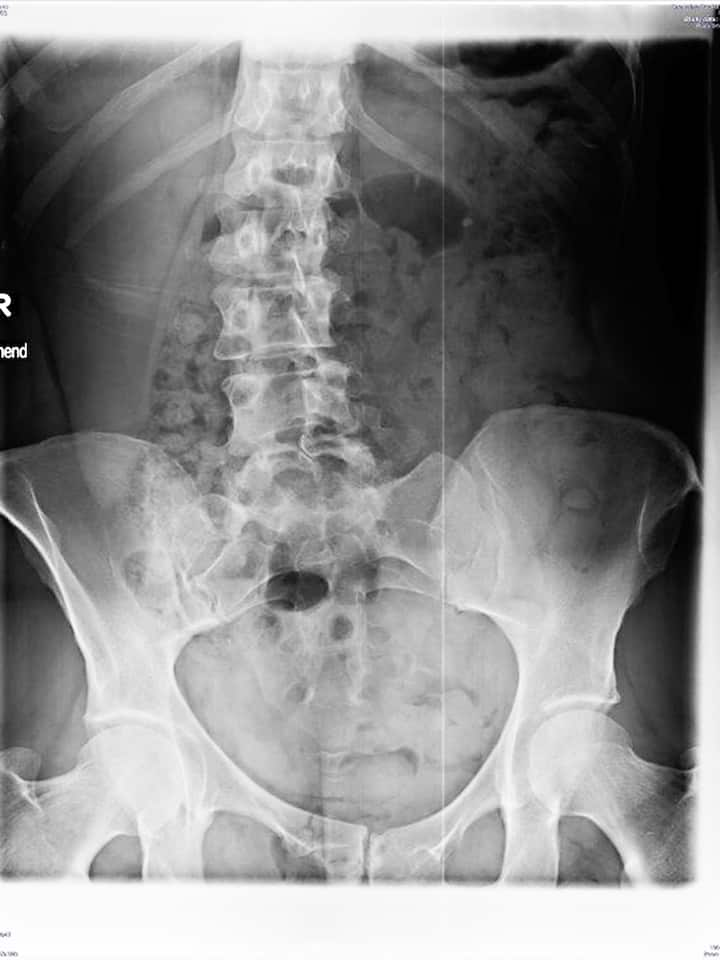

Eine belastete Bandscheibe könnte Ursache der Kreuzschmerzen sein: der Rücken der Autorin.

Die Röntgenbilder, die der 48-Jährige von meiner Wirbelsäule anfertigte, bringen Erstaunliches zutage: Ich habe eine Krümmung in der Lendenwirbelsäule («Skoliose»), einen zweigespaltenen Wirbelbogen am untersten Lendenwirbelgelenk («Spina bifida occulta»), und der linke Querfortsatz des untersten Lendenwirbels ist möglicherweise – das Röntgenbild zeigt es nicht eindeutig – mit dem Kreuzbein verwachsen («Sakralisation»). Zwischen «L4» und «L5», also dem vierten und fünften Lendenwirbel, ist der Abstand etwas weniger breit als bei den übrigen Gelenken. Die Bandscheibe dazwischen scheint belastet zu sein. Das könnte meine sporadischen Kreuzschmerzen erklären.

Betrübt betrachte ich die Bilder und frage mich, wie ich mit solchen Missbildungen im Rücken 50 Jahre lang aufrecht und schmerzfrei gehen konnte – und wie mich diese Wirbelsäule durch mein weiteres Leben tragen soll. Marco Vogelsang lächelt belustigt. «Schauen Sie», sagt er, «ich zeige Ihnen mal wirklich schlimme Bilder.»